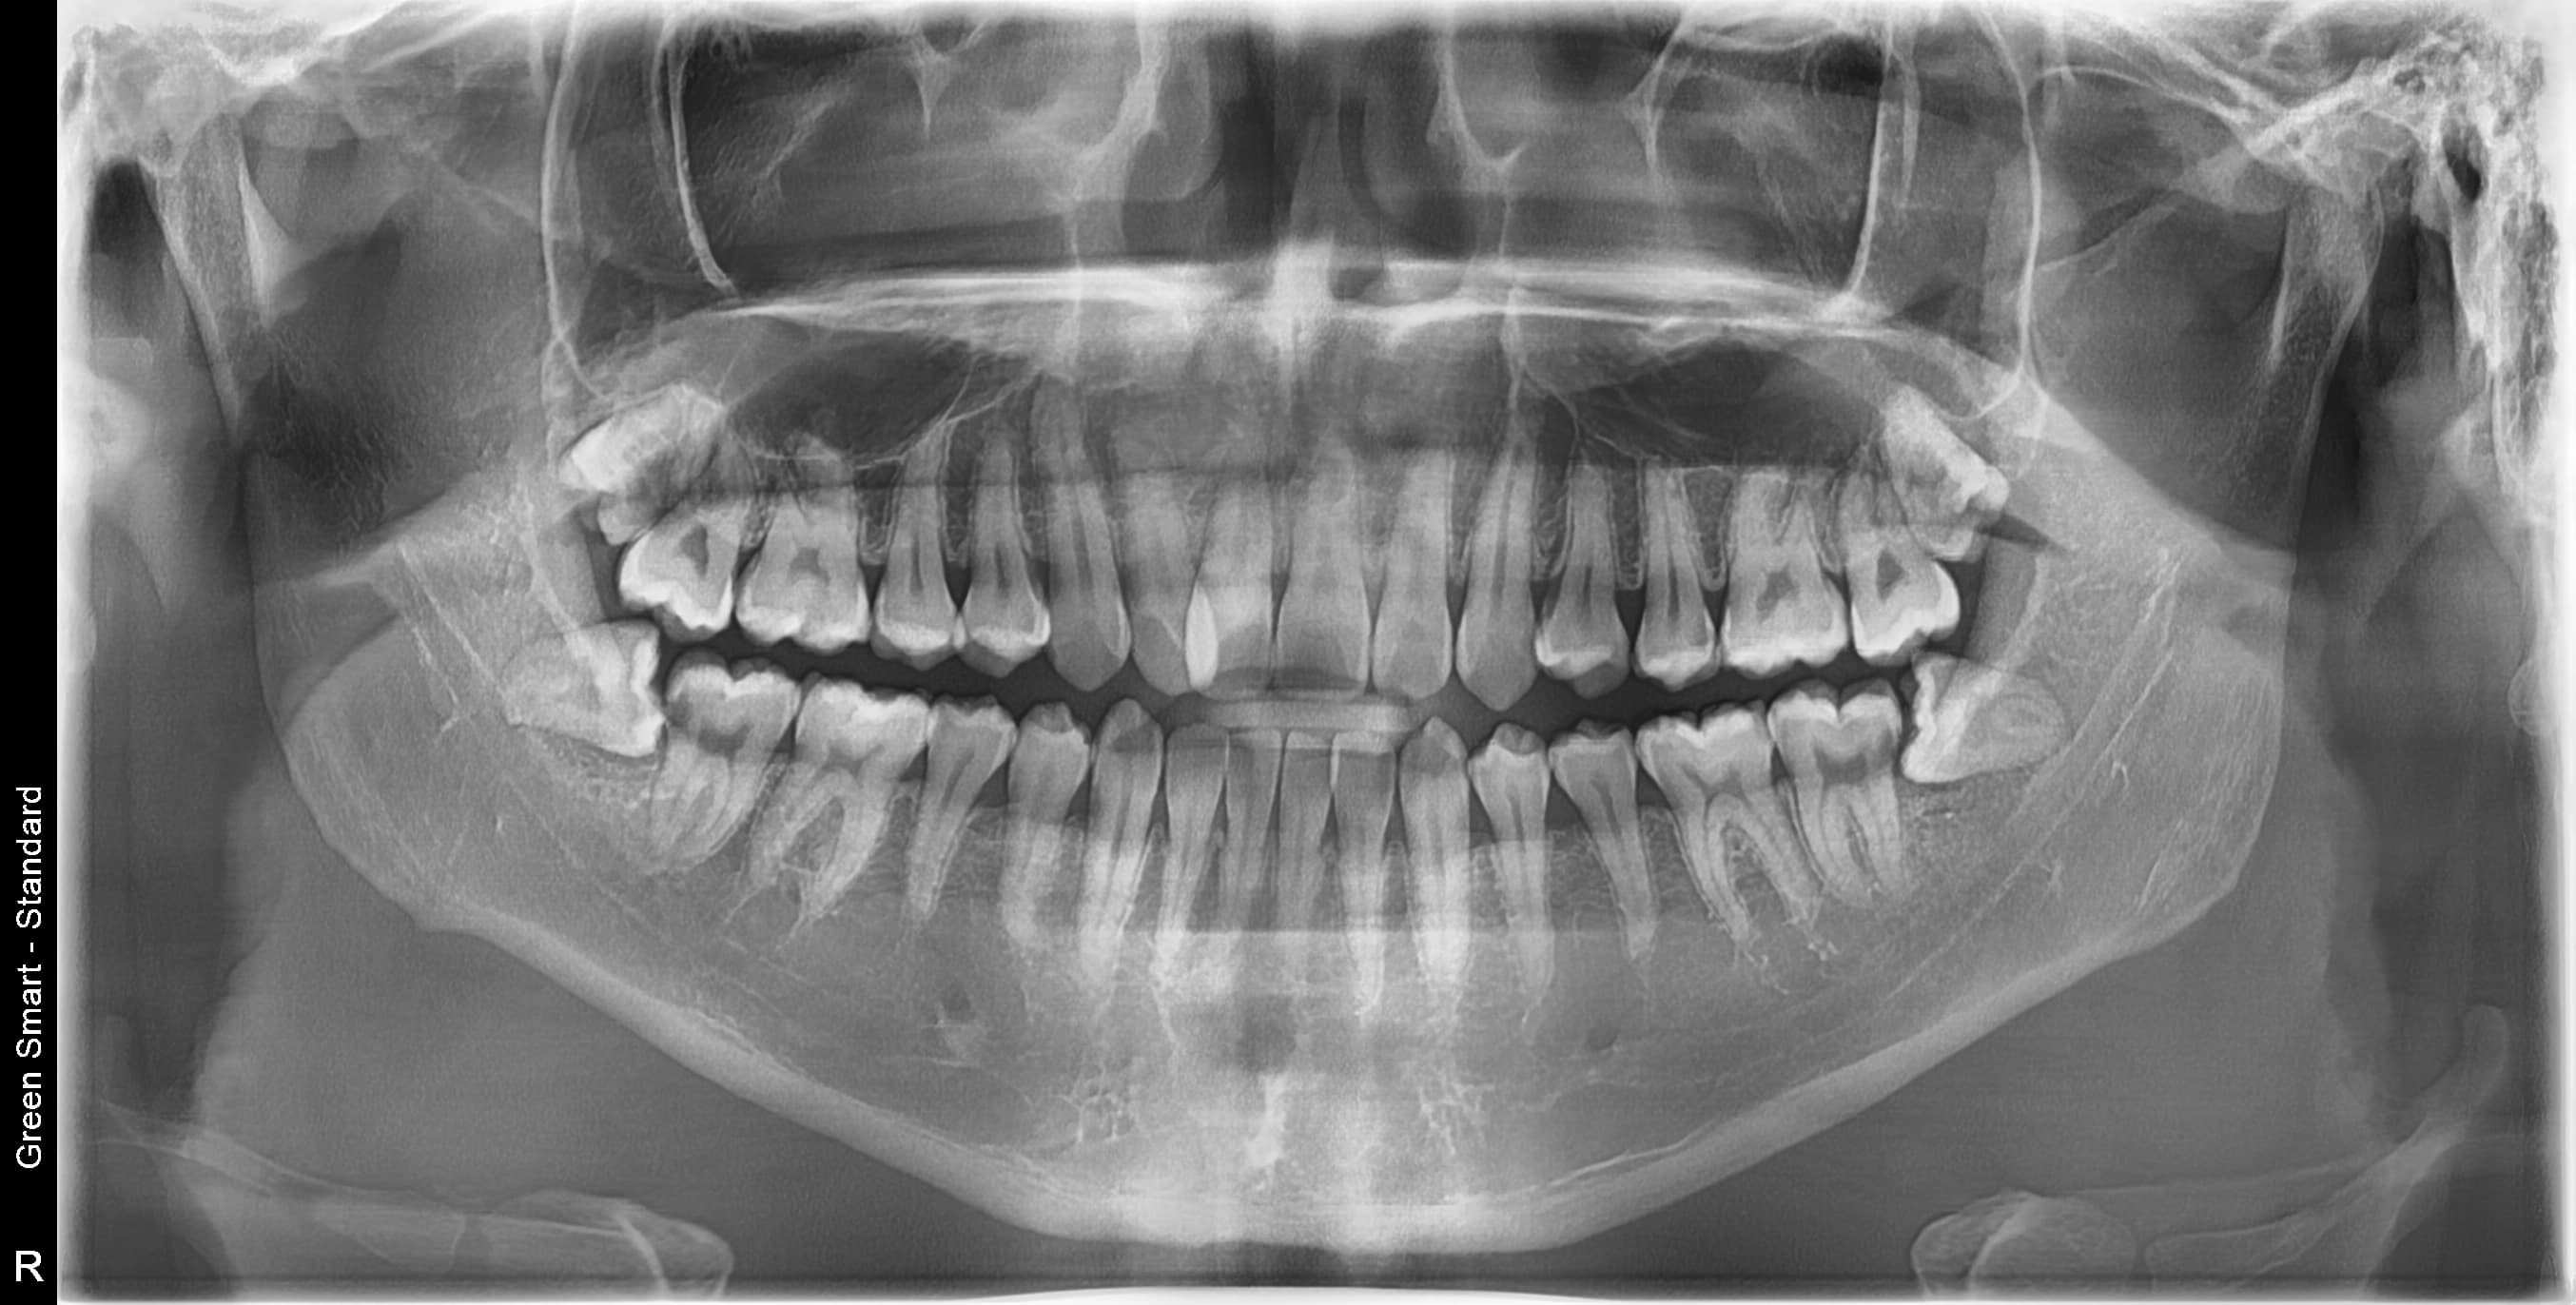

우리 병원 사랑니 발치의 특별함

2,700건 이상의 사랑니 발치 경험과 체계적인 시스템으로 차원이 다른 진료를 합니다

충분한 임상 경험

통합치의학 전문의 대표 원장의 안전하고 정확한 사랑니 발치

원스톱 진료 시스템

진단부터 발치, 사후 관리까지 당일 완료

왜 지금 발치해야 할까요?

사랑니 방치 시 발생하는 문제

급성 염증

심한 통증과 얼굴 부종

인접 치아 충치

옆 치아까지 손상

턱관절 장애

만성 두통과 턱 통증

치열 불균형

교정 치료 필요